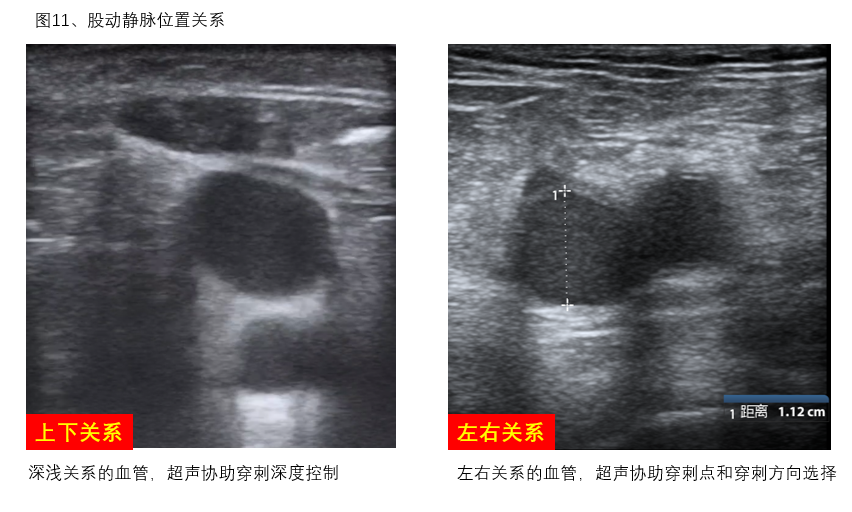

B、最佳穿刺点定位:观察拟穿刺动脉与伴行静脉之间的位置关系,寻找最佳穿刺点,若超声发现同侧股动静脉之间的距离较近或呈上下叠加关系,则需考虑引流管和回输管分别左、右双腿放置,避免穿刺置管造成局部血管损伤及其他并发症的发生(图11)。

图11